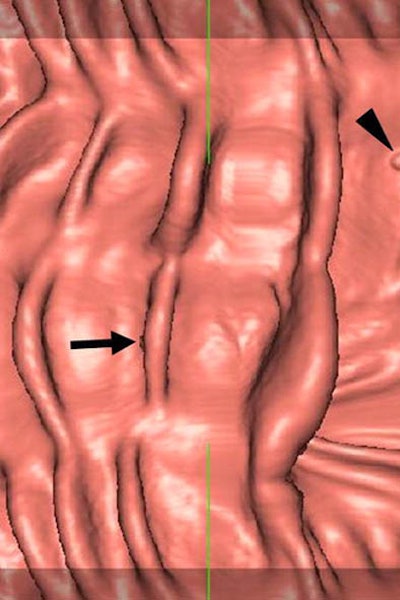

| Above, sessile 7-mm polyp in sigmoid colon of 60-year-old man. Virtual 3D views of supine (left) and prone (right) datasets show a small sessile polyp (arrow) in the sigmoid colon. Below, transverse 2D CT colonographic images of supine and prone (not shown) datasets also show the polyp (arrow) in the sigmoid colon. Bottom, conventional colonoscopic findings confirm the presence of the lesion (arrow). Biopsy was subsequently performed, and the final pathologic diagnosis was of an adenomatous polyp. Images courtesy of Dr. Se Hyung Kim. |